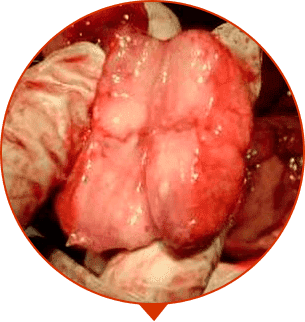

ONCOLOGY

Malignant tumor, the most common cause of death in men